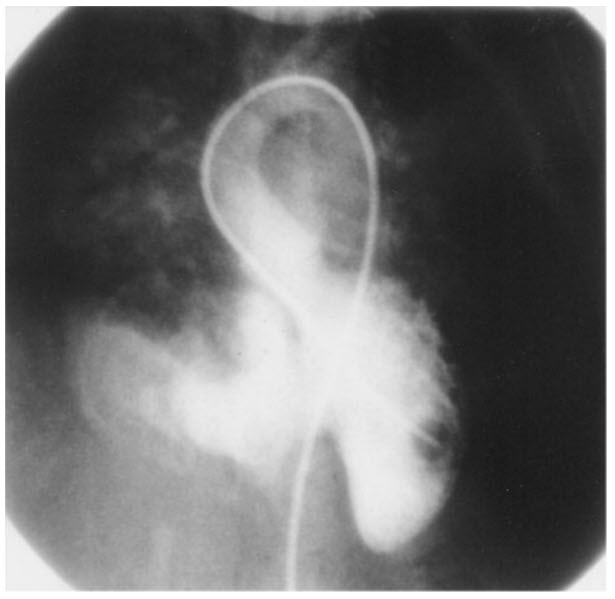

Match the following cardiac catheterization still-frame slide to it's respective diagnosis.

A. Coarctation of the aorta

B. Patent ductus arteriosus (PDA)

C. Hypertrophic cardiomyopathy

D. Pulmonic stenosis

E. VSD